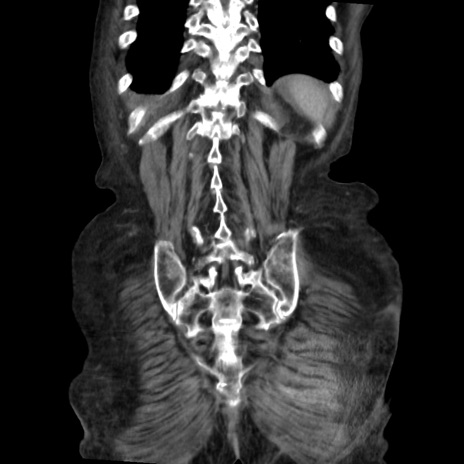

矢状断像